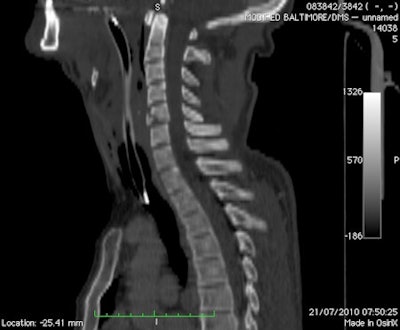

These two images are from a soldier in a vehicle hit by an improvized explosive device. Above: A lateral CT reformat of the cervical spine with an anterior inferior fracture of C5. Below: A coronal CT reformat of the sacrum and lumbar spine. The patient demonstrates a left vertical sacral fracture, left transverse fracture of L5, and burst fracture of L2. All images courtesy of Dr. Richard Graham.